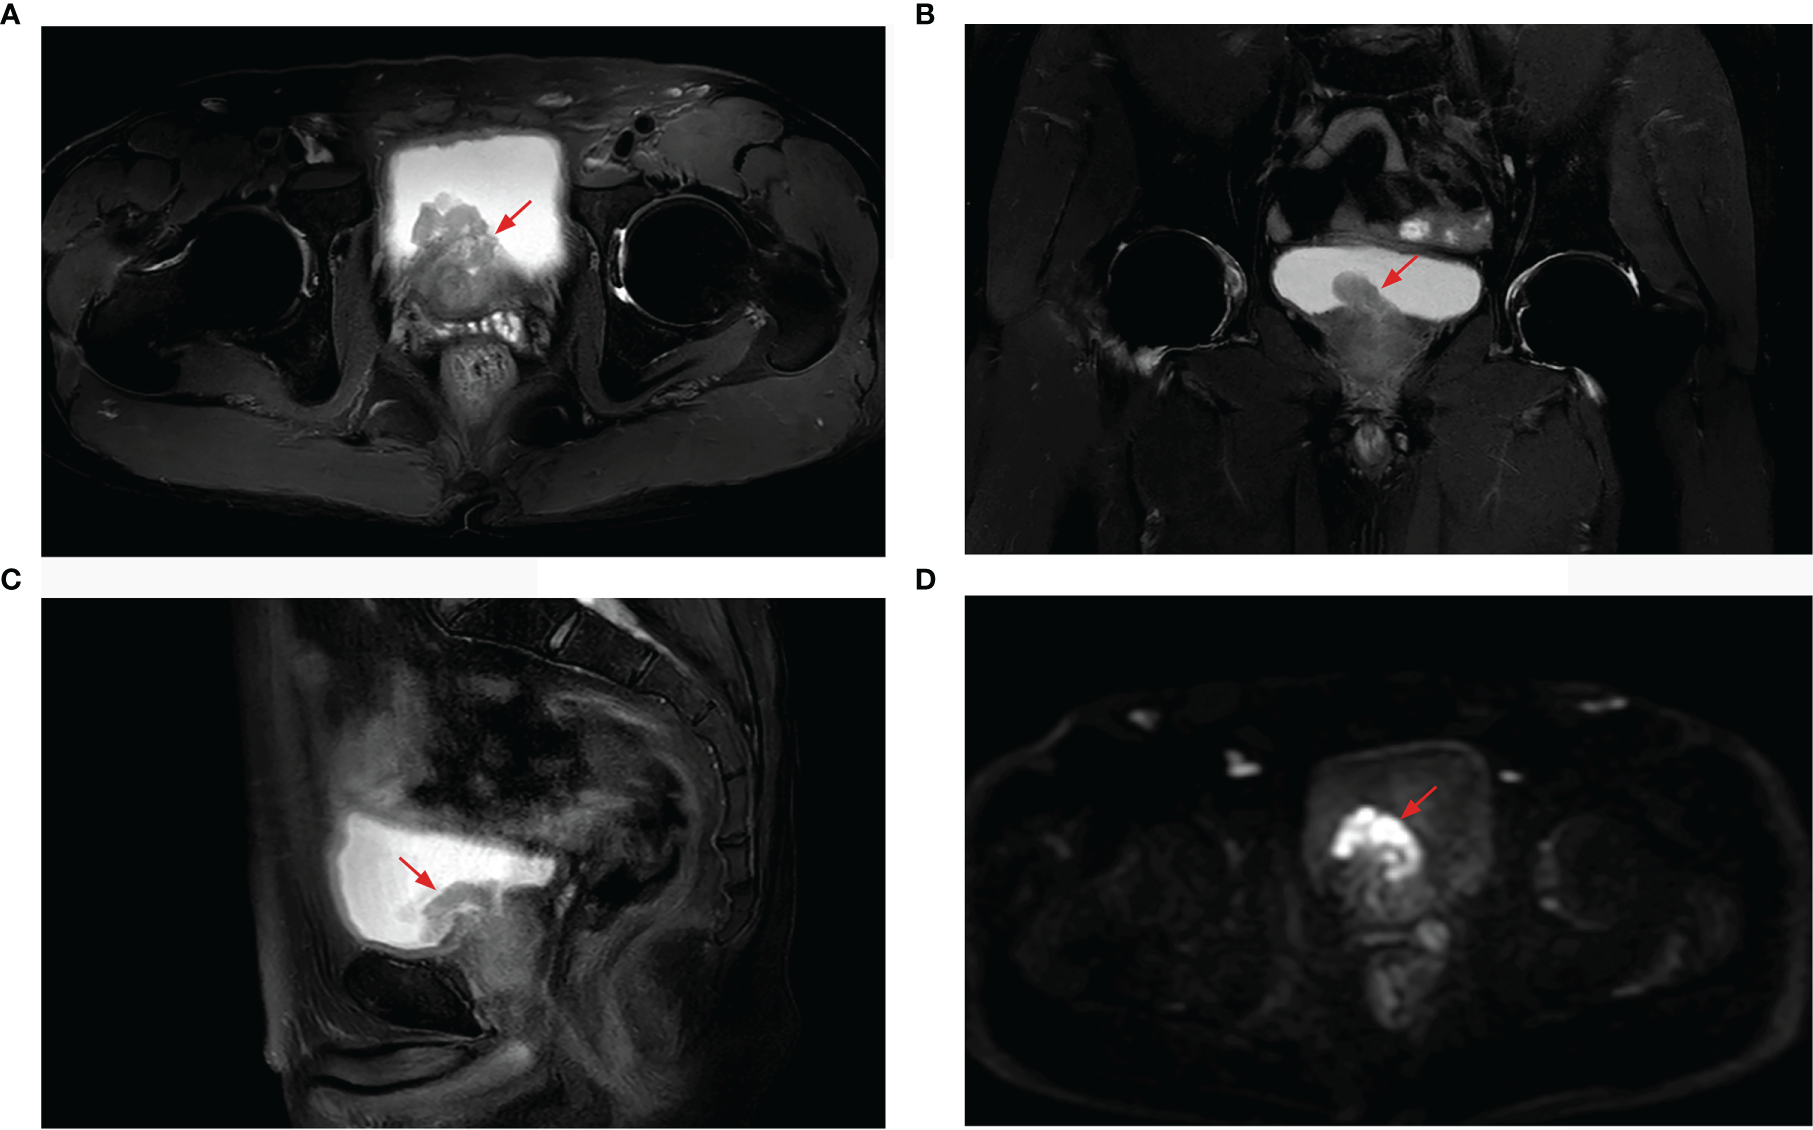

Figure 2

Prostate MRI revealing prostate cancer with bladder invasion, a marked hyperintensity on T2-weighted imaging [(A) axial, (B) coronal, (C) sagittal], and hypointensity on diffusion-weighted imaging (D).